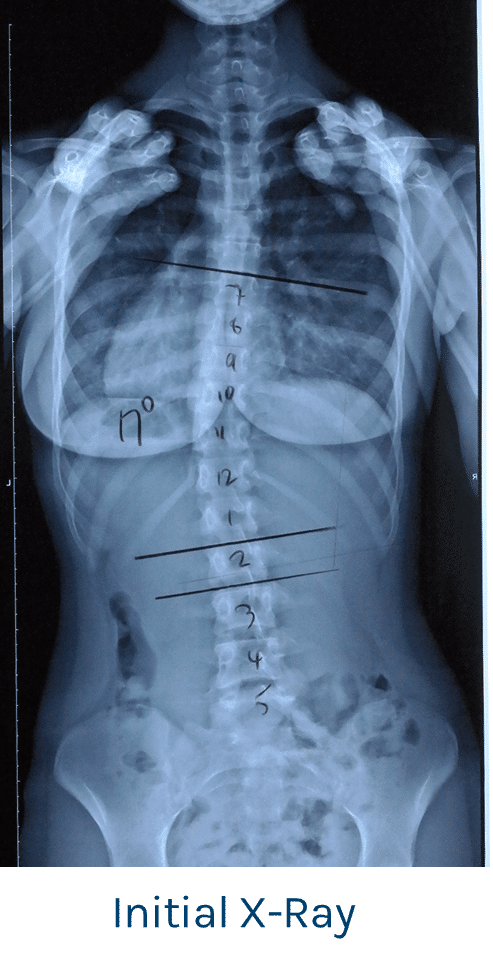

Patient aged 14 years of age with a primary thoracolumbar curve measured at 17 degrees (Cobb angle).

Patient was referred to a ScoliCare Clinic by an orthopaedic surgeon for exercise rehabilitation treatment for scoliosis. The patient presented with a left coronal imbalance which proved to be a primary left thoracolumbar curve measured at 17 degrees.

In this particular case the scoliosis was postural, and the presenting posture appeared more exaggerated than the X-ray showed. There was a noted hip asymmetry.

Over the 4 months of treatment, there was a gradual improvement in the patient’s posture and core stability. By the final session her posture had become a lot more centered and her waist and hips were now symmetrical. X-ray showed a reduction in the curve from 17.5 degrees to 13 degrees.